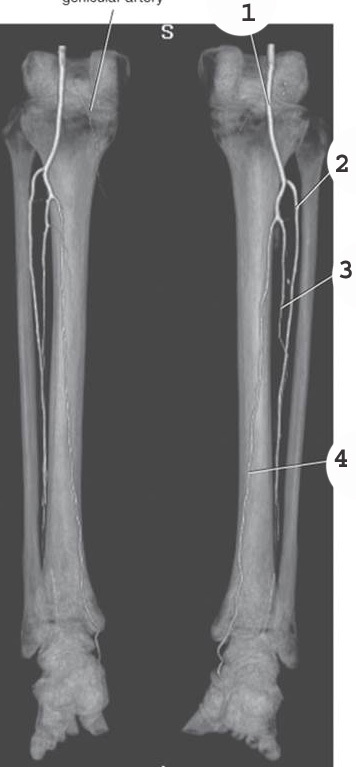

1

popliteal artery

2

anterior tibial artery

3

fibular artery

4

posterior tibial artery